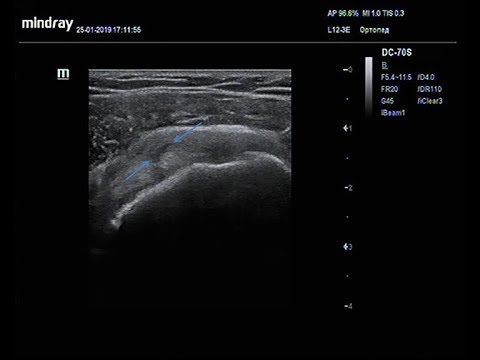

Сухожилие можно легко идентифицировать в межбуглерной борозде на переднебоковой стороне плечевой кости при нейтральном положении руки. исследованы как в поперечной, так и в продольной плоскостях [Рисунок и]. Важно не путать анизотропию из-за угла наклона зонда [Рисунок -] с тендинопатией [].Обычно вокруг сухожилия можно увидеть небольшое количество жидкости. Это можно легко отличить от тендосиновита, когда в жидкости есть внутренние эхо-сигналы с участками повышенного допплеровского кровотока.